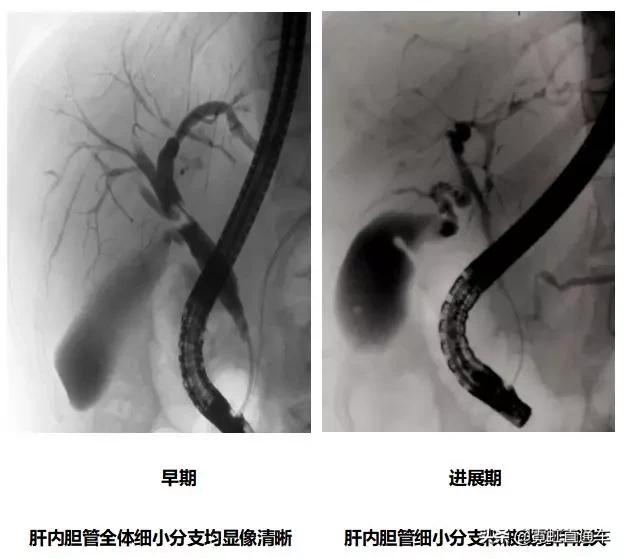

A.胆道影像学检查

1)特异性胆管征象

2)非特异性胆管征象

ERCP:胆管狭窄与扩张交互,呈串珠状改变

多发短小狭窄,胆管环状受累

PTCD:胆管呈边缘不整羽毛状

ERC:胆管壁呈憩室样突出